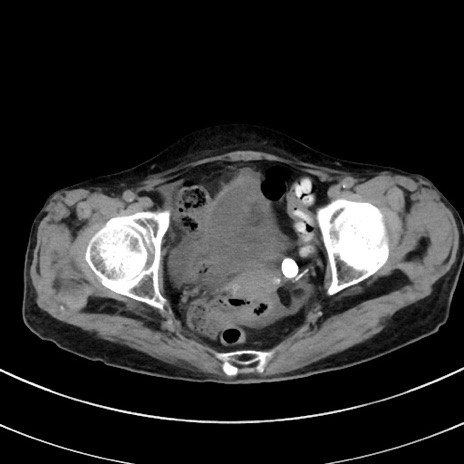

症例33(横断像)

【症例】70歳代 女性

【主訴】心窩部痛

【現病歴】延髄病変の精査・加療にて神経内科入院中。本日より心窩部痛あり。

【既往歴】虫垂炎

【身体所見】右下腹部を中心に圧痛と反跳痛あり。

【データ】WBC 10900、CRP 0.02